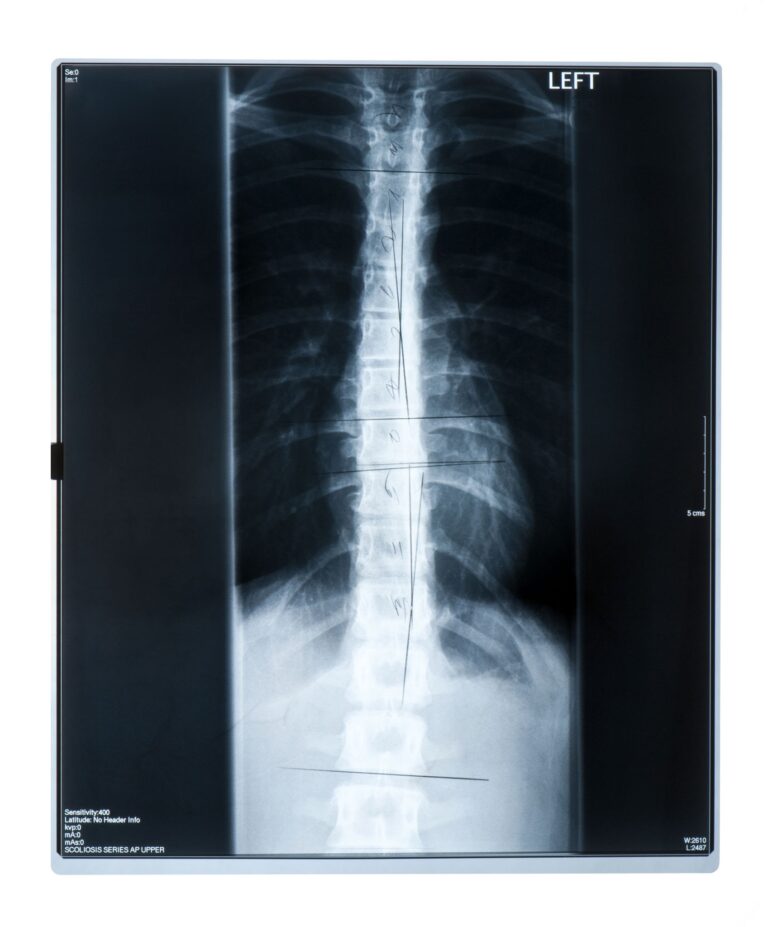

Der Goldstandard ist jedoch die bildgebende Diagnostik. Notwendig sind Röntgenaufnahmen der Wirbelsäule in Seitansicht.

Was sieht man im Röntgenbild?

Für die Diagnose sucht der Radiologe oder Orthopäde nach den Sorensen-Kriterien:

- Keilförmige Deformierung von mindestens drei benachbarten Wirbelkörpern mit mindestens 5 Grad.

- Eine verstärkte Brustkyphose über 45–50 Grad.

- Das Vorhandensein sogenannter Schmorlscher Knötchen: Vorwölbungen des Bandscheibenmaterials in den Wirbelkörper.

Bei neurologischen Symptomen (was sehr selten ist) wird eine MRT empfohlen. Als Physiotherapeut messe ich zusätzlich goniometrisch die Beweglichkeit der Wirbelsäule, um die Steifigkeit zu beurteilen.